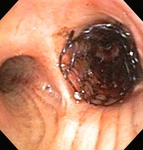

Bronchoscopic therapy for central airway obstruction of the right mainstem: stent placement

From the collections of Jose Fernando Santacruz MD, FCCP, DAABIP and Erik Folch MD, MSc; used with permission